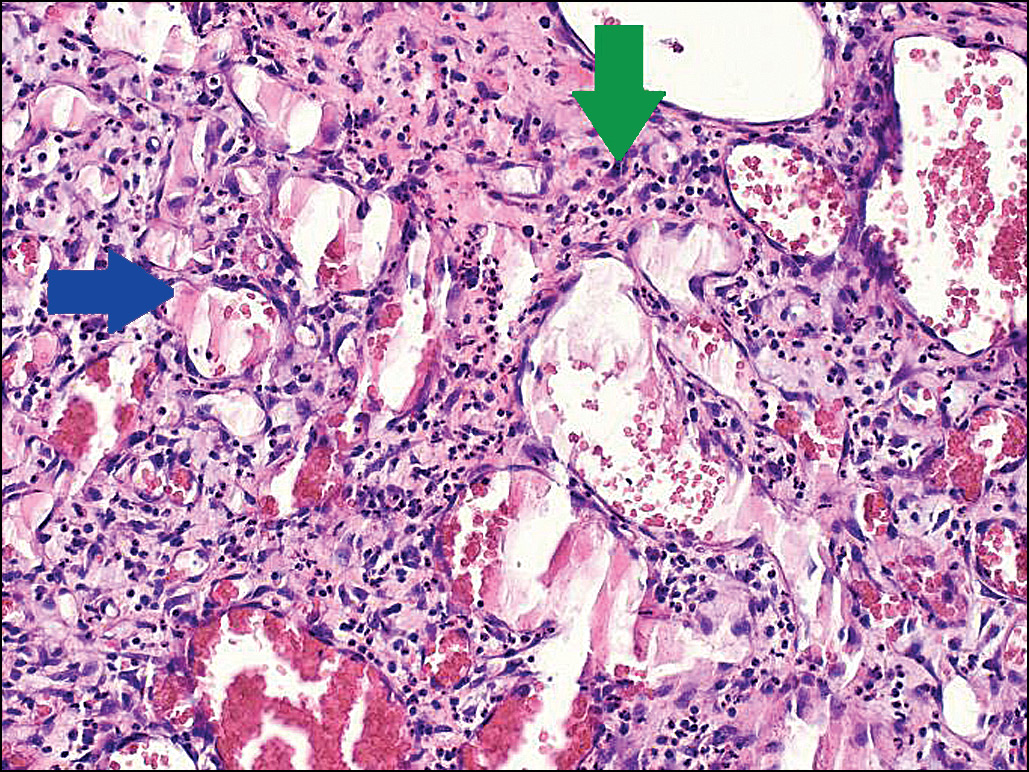

Рис. 3. Гистологический препарат. Опухоль представлена пол- нокровными капиллярами (синяя стрелка). В строме имеется выраженное смешанноклеточное воспаление (зелёная стрелка). Окраска гематоксилином и эозином. Ув. 200.

При микроскопическом исследовании опухоль хорошо отграничена от нормальных тканей, эпидермис над опухолью с признаками изъязвления (рис. 2). Основа опухоли представлена пролиферирующими мелкими капиллярами, имеющими вид многодольчатых структур, окружённых фиброзной или несколько отёчной стромой (рис. 3). Каждая долька гемангиомы образована крупным кровеносным сосудом. Клетки хронического и острого воспаления распределены в опухоли, преимущественно в её поверхностных отделах. Заключение: дольчатая капиллярная гемангиома (пиогенная гранулёма) кожи (см. рис. 3).